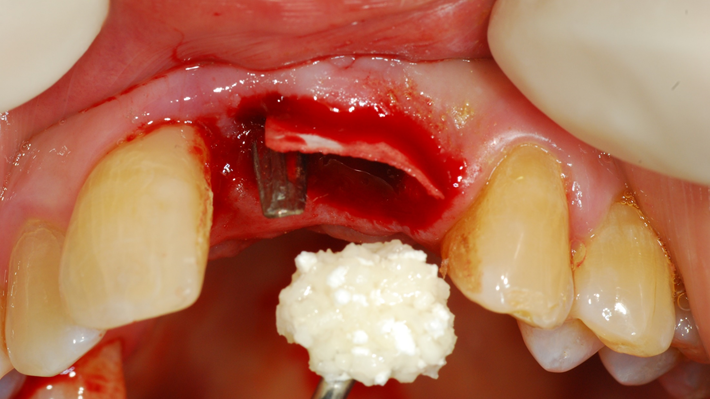

“Achieving a clean surface is the key to treating peri-implantitis!Using a titanium or NiTi brush for the decontamination process along with proper GBR can successfully restore the peri-implant environment. ”

Clinical case: Peri-implantitis treatment case using titanium or NiTi brush

- Courtesy of Dr. Dae-Hee Lee, South Korea -

Dr. Dae-Hee Lee,Maxillary Anterior,Peri-implantitis,Bone regeneration,Aesthetic zone,#21,#22,GBR,Titanium Brush Set

Titanium Brush Set